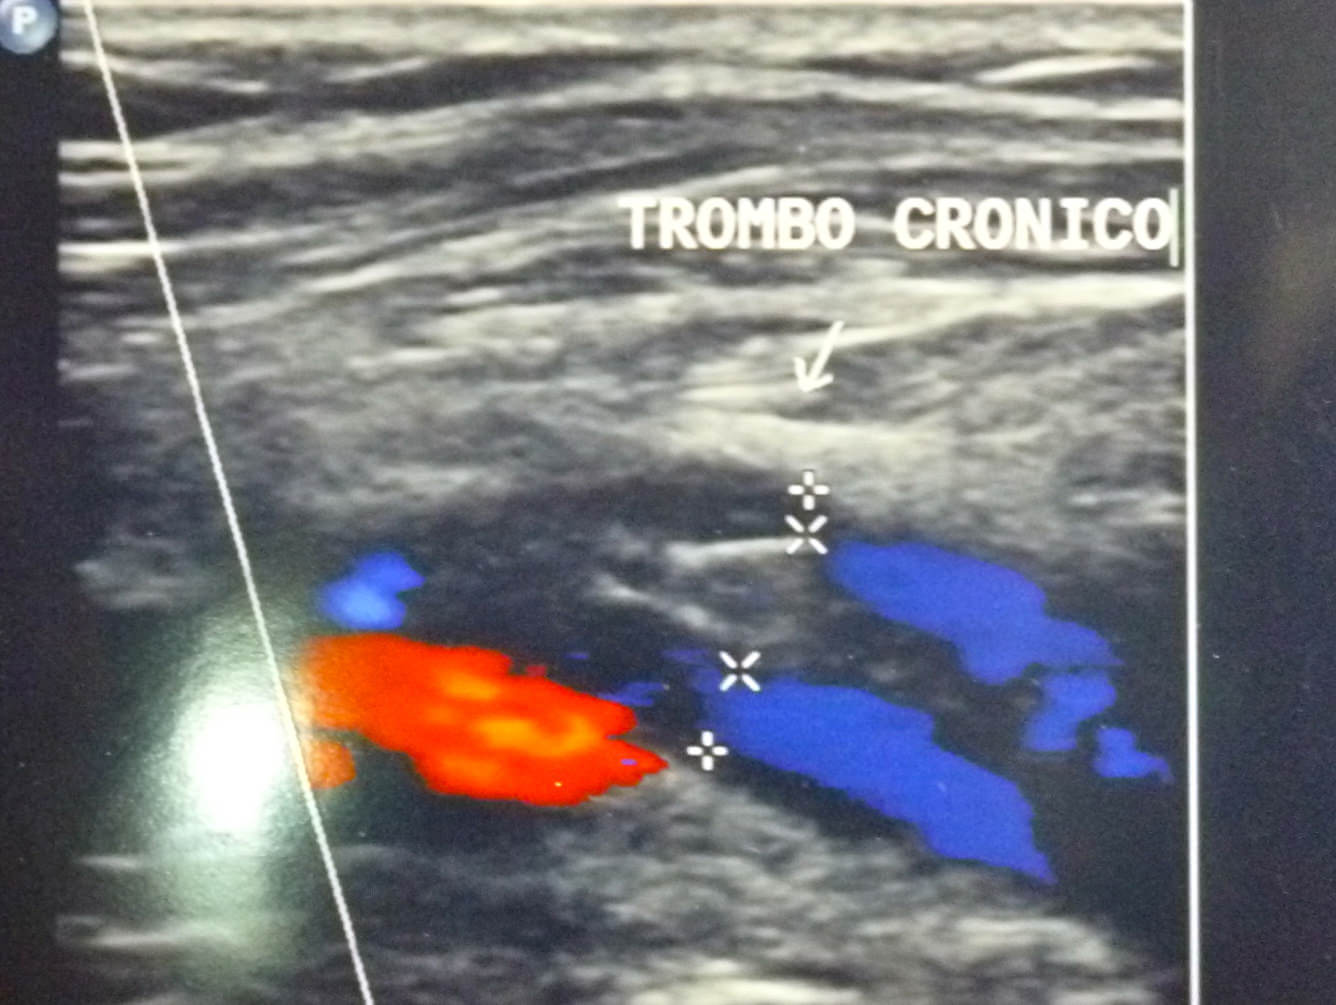

La ecografía dúplex puede mostrar la forma como fluye la sangre a muchas partes del cuerpo y es una opción menos invasiva que la arteriografía y la venografía. También puede determinar el ancho de un vaso sanguíneo y revelar cualquier obstrucción.

Se refiere al efecto Dúplex a que el médico quien realiza el estudio no sólo capta el espectro de ondas de flujo del Doppler sino que es capaz de visualizar la imagen bidimensional en tiempo real las diferentes estructuras anatómicas y en este caso las venas y las arterias.